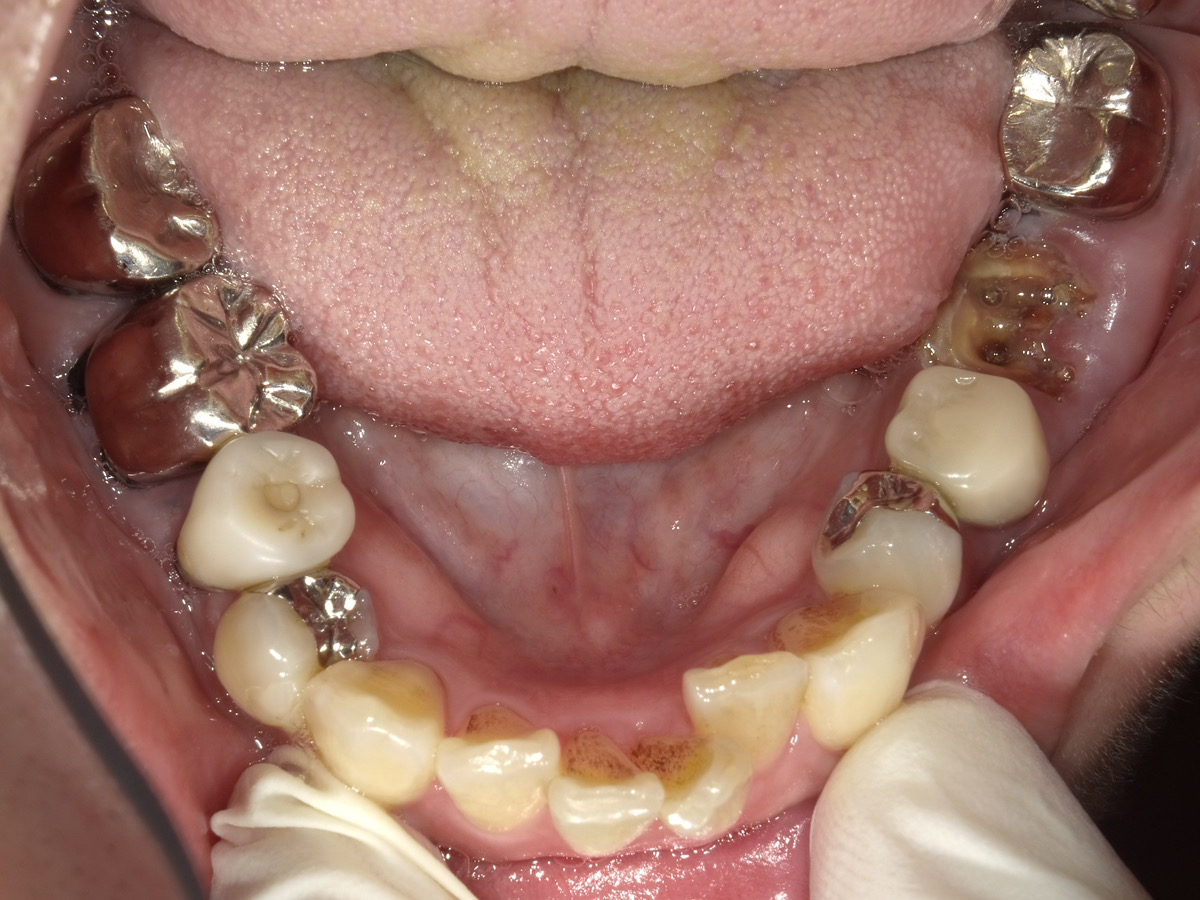

ご相談内容 左下奥歯の被せ物が土台ごと取れてしまいどうにかならないかと相談に来られました

考えられる原因はいくつかあります。

• 被せ物の中で虫歯が進んでいる

• 被せ物を支えている歯が弱くなっている

• 接着剤が長年の使用で劣化している

といったケースが多いですね。

これから中の歯の状態をしっかり確認していきます。